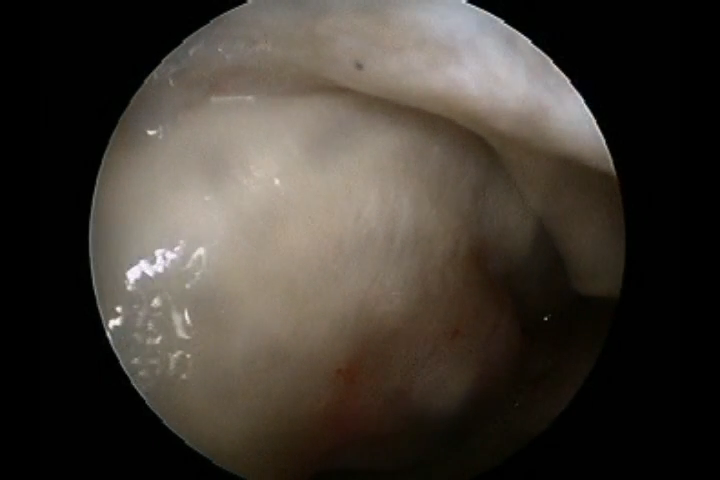

There used to be a common consensus that ACL reconstruction of knee should not be done in old age, this idea has now largely been debunked with statistical evidence. this 68 year old man with a traumatic anterior cruciate ligament tear had intact lateral and medial meniscus and quite normal cartilage in the weight bearing areas of knee, under such circumstances arthroscopic ACL repair should be done for a better outcome for the knee